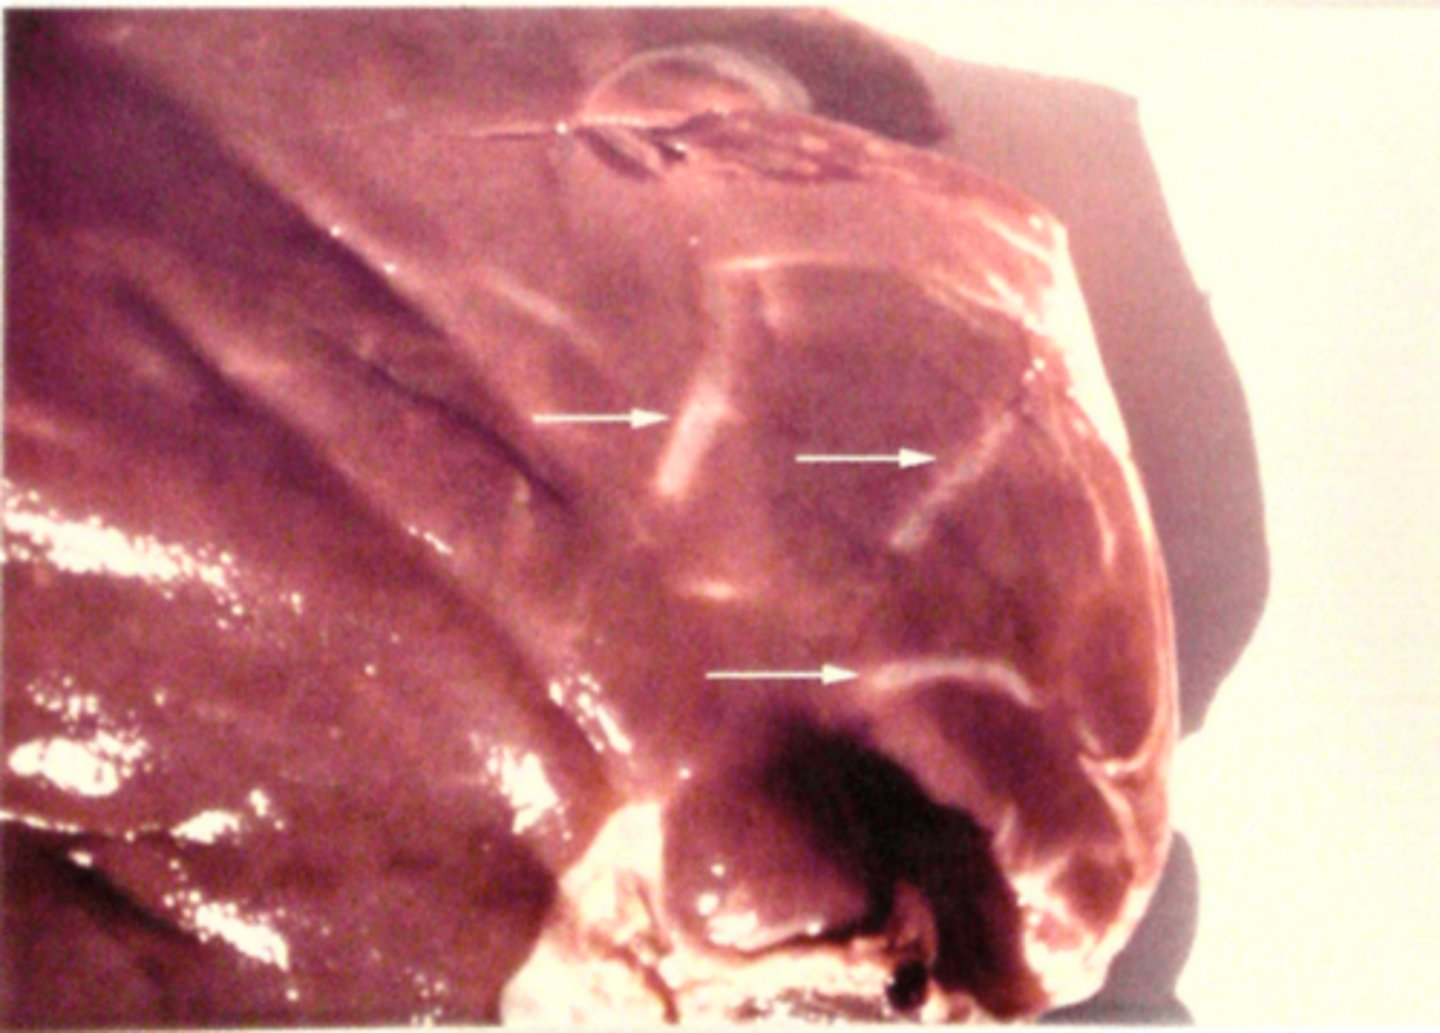

kronisk fibroniserende cholangioheptatitis (pile)

Ætiologi: Dicrocoelium dendriticum (den lille leverikte)

Lever fra får, hvad er den patoanatomiske diagnose og ætiologien?